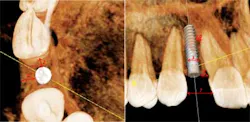

The orthodontist and the surgeon must also take into account the space appropriation in the interradicular area as well. The minimum spacing between the roots is generally 5 mm. This amount of space will allow the implant to be surrounded by 0.75 mm and 1.0 mm of bone, which is sufficient to support normal functional loading and ensure good long-term osseointegration. (22) During the space opening aspect of orthodontic care, the orthodontist must make a compensating bend to diverge the roots, especially when canines are initially distal angulated, since the canine root apex inevitably lags behind the crown when distalized. The orthodontist also has to pay particular attention to the skeletal relationship of the patient in these cases because in an Angle Class III tendency type case, the maxilla is narrow and the crowns tend to be tipped labially, which in turn results in adequate space for the restoration but insufficient space at the apex for fixture placement and may necessitate an alternative type of restoration or a shorter implant fixture. (3,6)

In any case, but especially Angle Class III cases, it is good practice for the restorative dentist or surgeon to take a periapical radiograph prior to the removal of the orthodontic appliances to ensure that adequate interradicular space has been established. Once the root position has been confirmed and appliances are removed, it becomes especially important to establish a retention protocol that will prevent relapse of the root position. Removable appliances are adequate to maintain the interradicular spacing in the short-term, but many times these cases need to be retained for a number of years until growth is complete and a more long-term provisional is recommended. In cases with a high relapse potential, a resin-bonded fixed partial denture should be considered. This type of restoration has the advantage of being esthetic, conservative, and eliminates compliance issues, all while maintaining the established tooth positions and site development.

and a narrow maxilla limits the orthodontist’s ability to torque the

roots and creates a convergence of the roots, which limits the

apical interradicular space for implant placement.